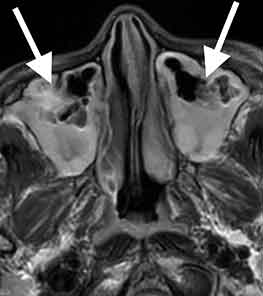

頭部MRI検査を行いました。

両側の上顎洞という場所に感染を起こして、膿が貯まっていました。副鼻腔炎という状態で、顔の痛みの原因となります。